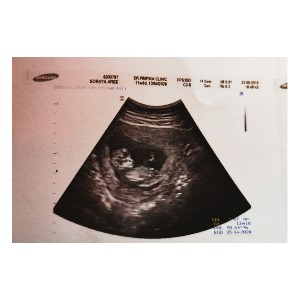

ตอนนี้ 11weeks ค่ะ

12 สัปดาห์ค่ะ